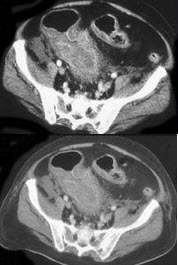

男性,50岁。消瘦、乏力半年,间断性上腹胀痛伴黑便2周。发育正常,体形消瘦,贫血外貌,皮肤无黄染,腹平坦,腹肌软,上腹偏右压痛,肝脾肋缘下未触及。低张气钡双重造影示十二指肠降段肠壁僵硬,蠕动消失,肠腔不规则狭窄。胃镜检查如下图,下列正确的是()。

A:十二指肠腺癌可能大

B:卓-艾综合征可能大

C:该病可导致黄疸

D:该病以中年人多见

E:该病首选手术治疗,无手术指征者可考虑放、化疗